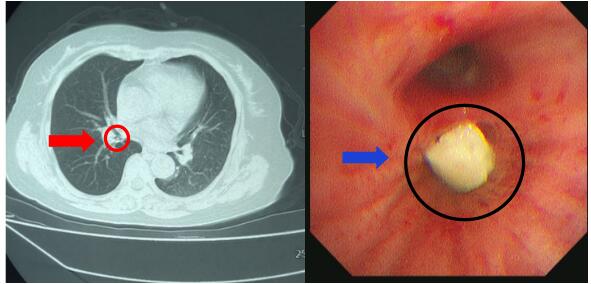

患者,男,58岁,因“咳嗽、咳痰3天“入院。入院后查胸部CT发现右肺下叶基底段占位。

为了进一步明确,我们进行气管镜检查,使用超细支气管镜,于右肺下后基底段亚支,看见新生物活检后病理诊断为“鳞状细胞癌”。